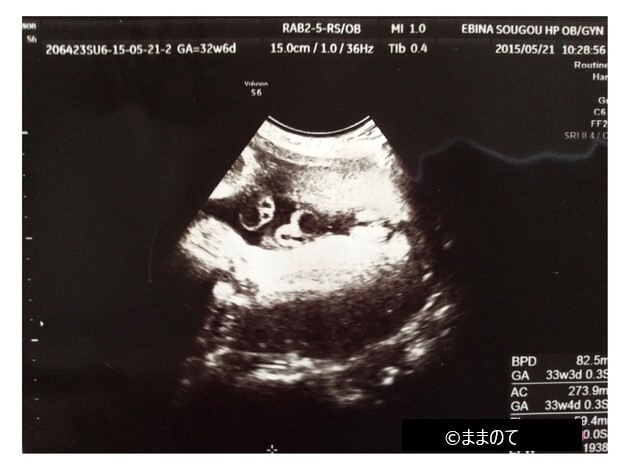

【女の子のエコー】妊娠32週

男の子と比べると、女の子の外性器は少しわかりづらいかもしれません。しかし、妊娠週数が進み赤ちゃんの身体が大きく成長してくると、女の子のおまたの形がエコー写真にくっきりと浮かび上がります。写真では、コーヒー豆のような外性器が右側に確認できますね。